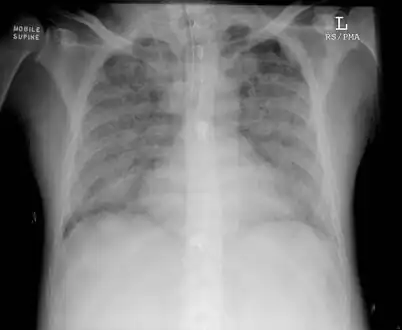

| Chest x-ray of person with severe ARDS demonstrating widespread "ground-glass" appearing opacities in both lungs. | |

Medical imaging

Radiologic imaging has long been a criterion for diagnosis of ARDS. Original definitions of ARDS specified that correlative chest X-ray findings were required for diagnosis, the diagnostic criteria have been expanded over time to accept CT and ultrasound findings as equally contributory. Generally, radiographic findings of fluid accumulation (pulmonary edema) affecting both lungs and unrelated to increased cardiopulmonary vascular pressure (such as in heart failure) may be suggestive of ARDS. Ultrasound findings suggestive of ARDS include the following:

- bilateral opacities on chest imaging (chest radiograph or CT) not explained by other lung pathology (e.g. effusion, lobar/lung collapse, or nodules)